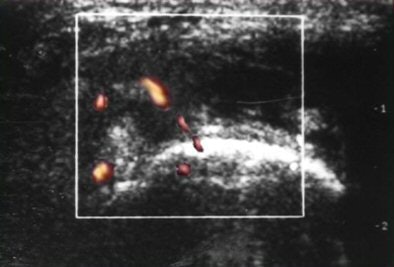

![]() |

| Baseline PDS of right knee reveals marked vascular signals. |

| Follow-up images of the same patient at the end of the second (above) and sixth (below) month after therapy demonstrate significant decrease in vascularity. |